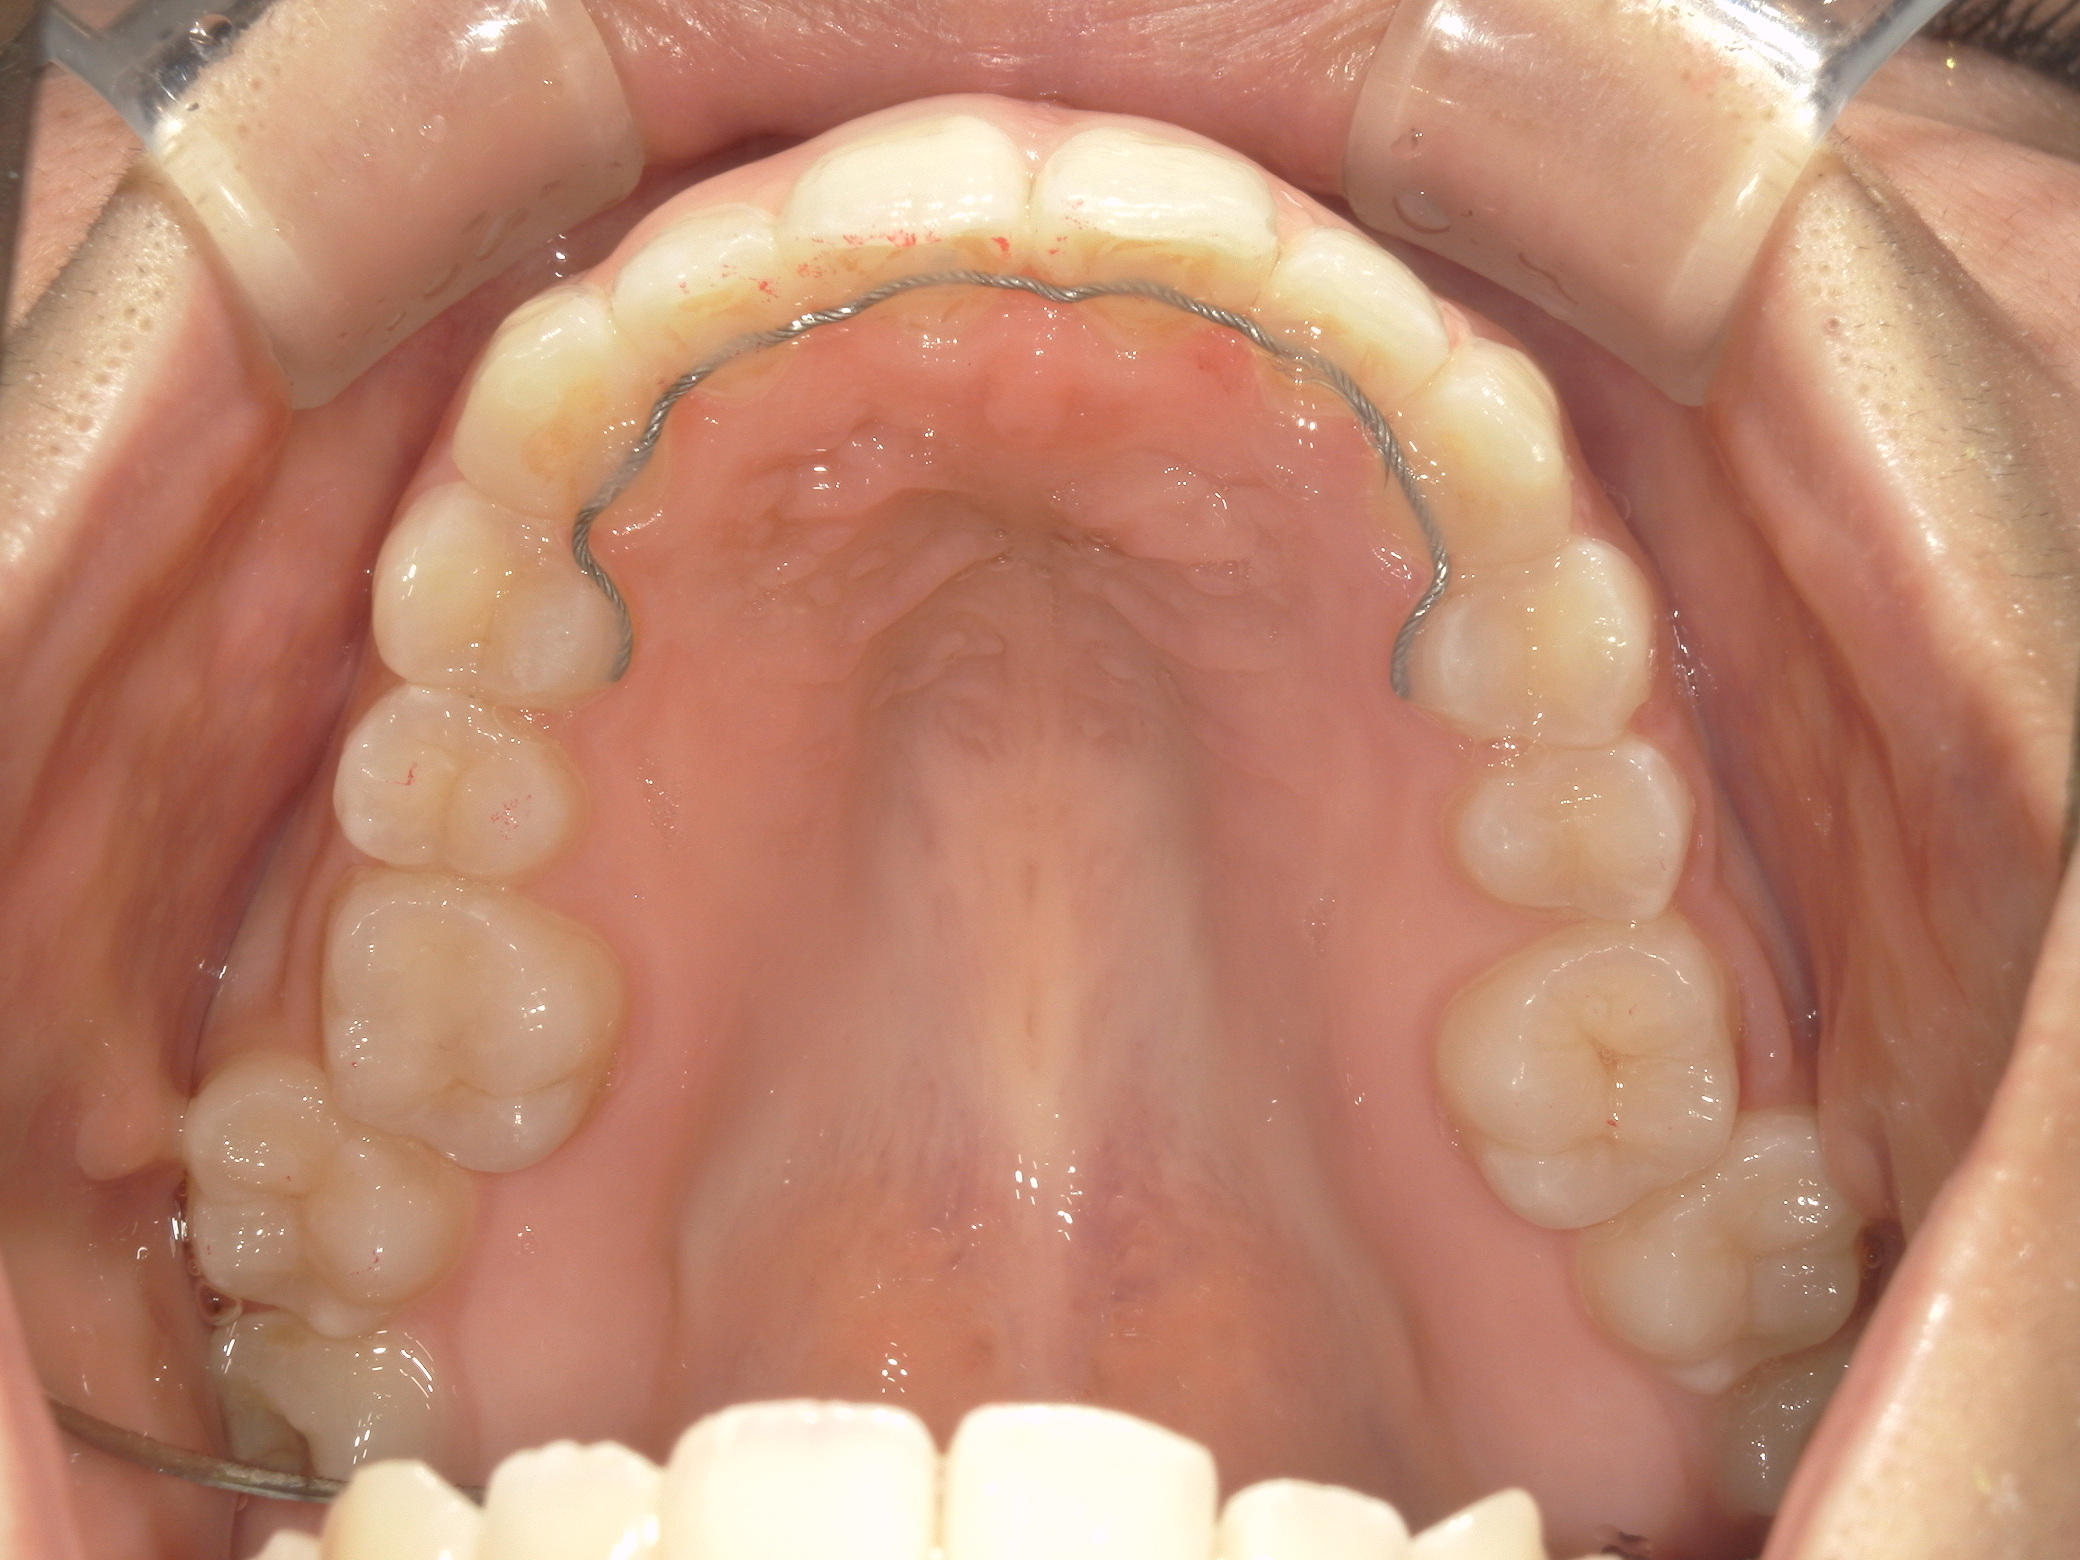

プチワイヤー矯正 症例(54)

ミニインプラント(2本)、スライスカットを併用。

治療の流れ

カテゴリー : ガタガタ(叢生)